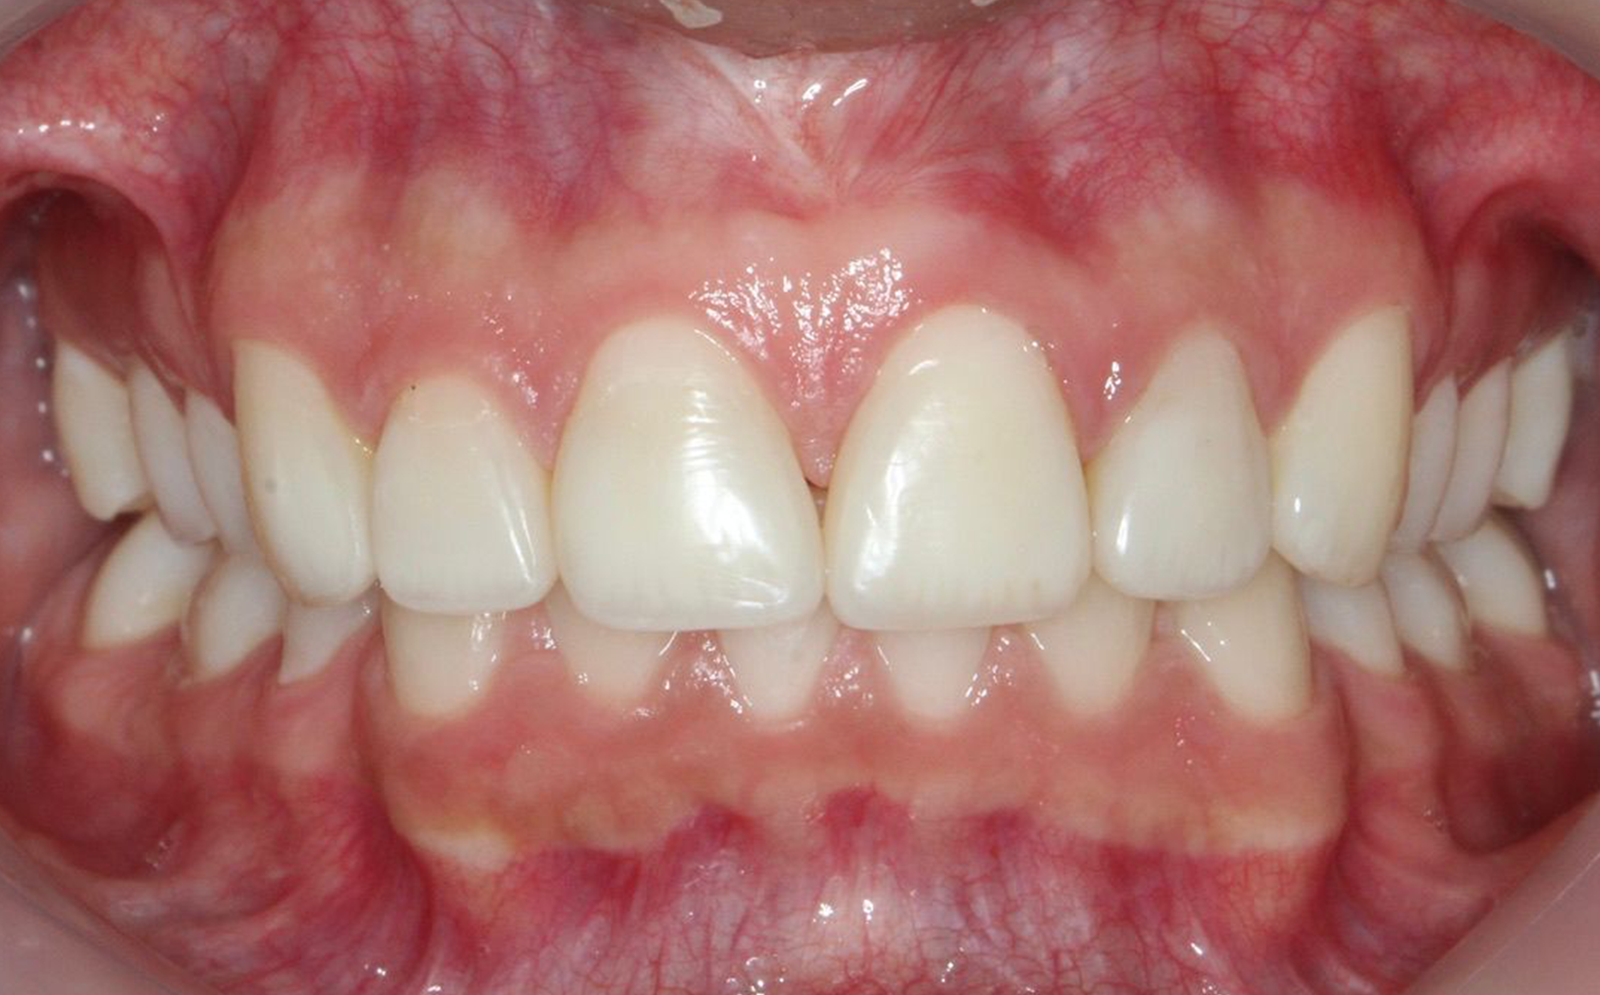

Restauración completa para dientes dañados

Las coronas dentales son restauraciones completas que cubren totalmente un diente que ha sido dañado o debilitado, o que ha recibido un tratamiento de endodoncia. La función principal de las coronas es proteger el diente, devolverle su forma y función, y evitar que se fracture. Existen varios tipos de coronas, y cada una tiene sus ventajas según las necesidades de cada paciente.

Antes

Procedimiento

Después